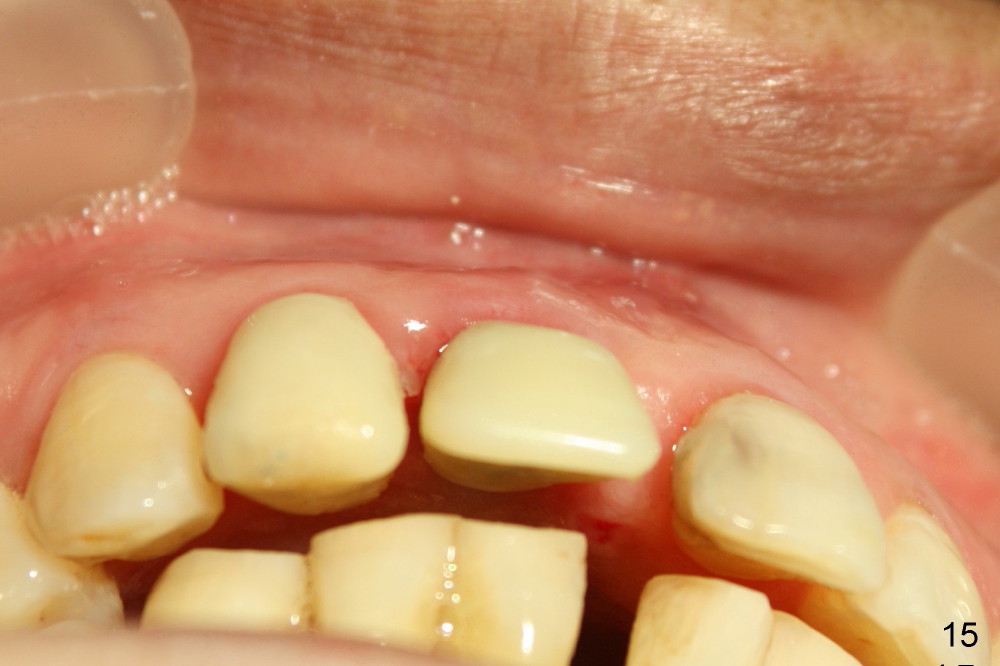

The patient returns for follow up 8 days postop and the labial margin of the provisional looks long. The metal crown is changed to a provisional at the visit. Eight days later, the provisional at the site of #8 is removed for labial margin trimming; the labial gingiva heals (Fig.14 *). The labial plate remains slightly convex (Fig.15). The labial margin of the provisional at the site of #8 is at the same level of that of #9.